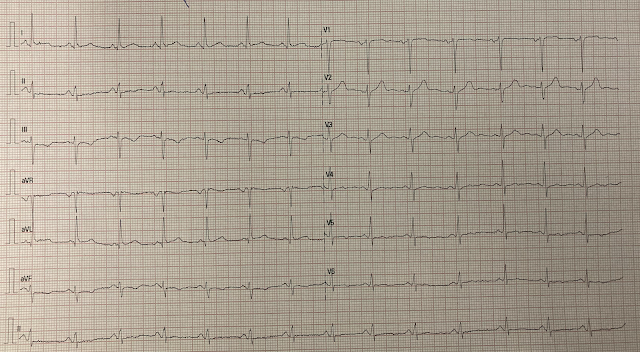

"Yesterday we received a 62 yo man with diabetes, hypertension and smoker. He reported typical chest pain since 4H AM and arrived at our ED at 10h with ongoing chest pain. The first ECG (10h14) showed TWI in inferior leads."

Time zero:

What do you think?

ECG #1 — shows such subtle but-definitely-present changes in multiple leads:

- The rhythm is sinus at 80-85/minute. Intervals (PR-QRS-QTc) are normal. The frontal plane axis is leftward — but not leftward enough to qualify as LAHB (since the QRS is not predominantly negative in lead II). There is no chamber enlargement.

- There are small, narrow Q waves in leads I, aVL. Whether these are normal septal q waves — or something more — is not initially apparent.

- R wave progression is normal.

In a higher-risk patient with new CP — leads I and aVL caught my "eye", as there is subtle straightening of the ST segment takeoff in both of these high-lateral leads.

- That this finding in leads I and aVL is likely to be "real" — is supported by ST segment coving and T wave inversion in leads III and aVF (with ST flattening in the 3rd inferior lead = lead II).

- Further support of an acute ongoing event is provided in lead V2 — which manifests a disproportionately "bulky" T wave, that is clearly "fatter"-than-it-should-be at its peak given the size of the QRS in this lead (BLUE arrow in V2).

- As we often note in Dr. Smith's ECG Blog — there normally should be slight, upward sloping ST elevation in leads V2 and V3. The YELLOW arrow indicates a lack of this slight normal ST elevation in lead V3.

- The remaining 4 chest leads (V1; V4,5,6) — all show abnormal ST segment flattening.

Impression of ECG #1: Although ECG changes in this initial tracing are subtle (and criteria for a STEMI are clearly not met) — 11/12 leads show ST-T wave abnormalities in this higher-risk patient. I was therefore suspicious of a postero-lateral OMI — which would localize the "culprit" artery to the LCx (Left Circumflex).

- I wondered if the "bulky" upright T wave in lead V2 might be the result of some spontaneous reperfusion (which is why it would be so helpful to find out if the patient's CP had decreased).